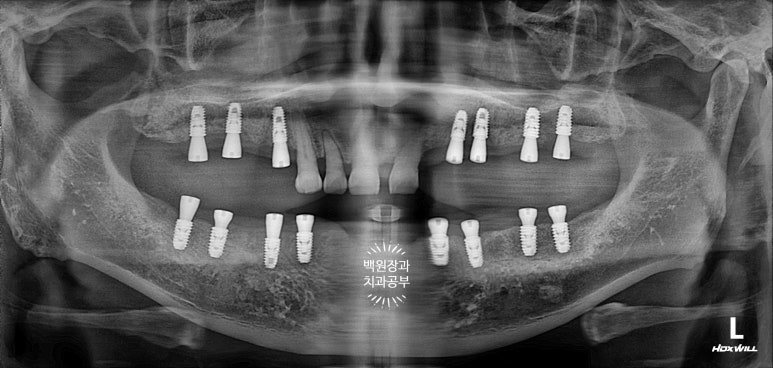

위턱 임플란트 수술 직후 파노라마 엑스레이 사진입니다.

처음 오셨을 때 갖고 계셨던 치아 중 흔들리지 않고, 비교적 제 위치를 잘 유지하고 있던 위턱 앞니 네개만 남겨놓았었네요...

건강한 사람은 위턱치아 14개, 아래턱치아 14개 총 28개의 치아를 갖고 살아갑니다.

그를 위해 위턱에 총 7개의 임플란트를 심어드렸었네요.